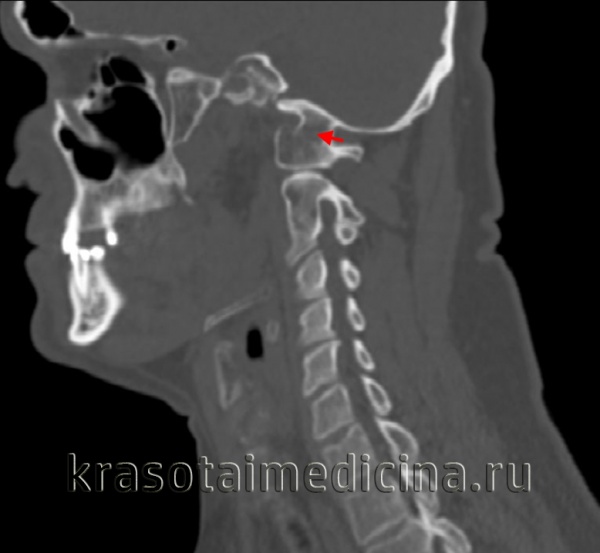

(Слева) На фронтальной томограмме, полученной через зубовидный отросток, отмечается латеральное смещение боковых масс С1 относительно боковых масс С2.

(Справа) На аксиальном Т2-ВИ пациента со взрывным переломов С1 видна интактная поперечная связка атланта. Обратите внимание на отрывной перелом костного фрагмента в области прикрепления этой связки при сохранении целостности самой связки.